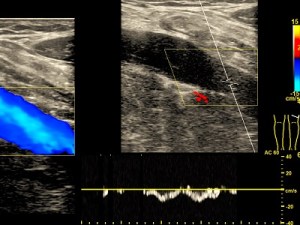

Obszary anatomiczne-badania dopplerowskie

Doppler tętnic szyjnych

Badanie wykonywane jako przesiewowe do wykrywania małych zmian miażdżycowych i czynników ryzyka choroby wieńcowej. Wykonywane też z powodu zawrotów głowy w celu oceny przepływów w tętnicach kręgowych.

Zapis dopplerowski z tętnicy- małe zmiany miażdżycowe.

Doppler tętnic kończyn dolnych

Wykrywa zmiany miażdżycowe i zwężenia oraz niedrożności w tętnicach.

Zapis dopplerowski z tętnicy- duże zmiany miażdżycowe ze zwężeniami.